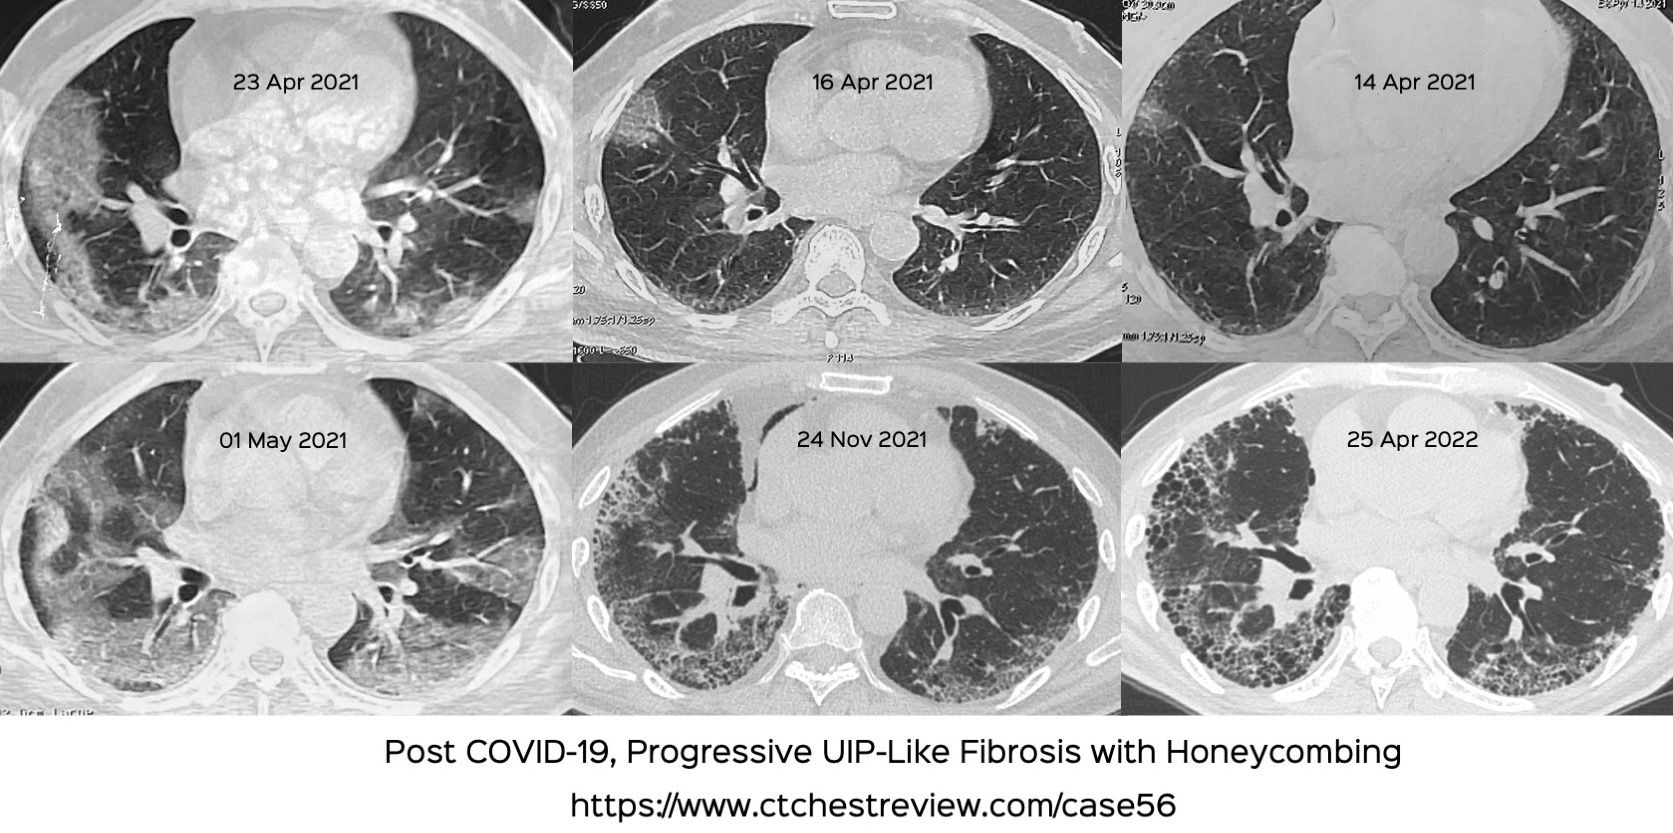

Case 56 Unusual Progressive UIPLike Fibrosis Following COVID19

Case 56 Unusual Progressive UIPLike Fibrosis Following COVID19 Ild Radiology Uip usual interstitial pneumonia (uip) is not a disease, it is a histopathologic and radiologic pattern of interstitial lung. Uip has distinctive hrct findings. a substantial proportion of cases of usual interstitial pneumonia (uip) are due to connective tissue disease. a substantial proportion of cases of usual interstitial pneumonia (uip) are due to connective tissue disease (ctd). If. Ild Radiology Uip.